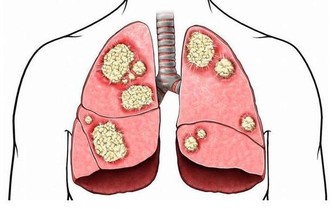

特別要說明的是,大腸癌也會導致慢性腹瀉。

不過一般來說,如果是因大腸癌導致的腹瀉,常常水性糞便中還混雜著血液,排便後還有糞便殘留的感覺,同時腹瀉與便秘交替、反復發生。

具體來說,大腸癌通常有以下症狀:便秘和腹瀉反復發生、有血便和便血、糞便很細、排便不爽、總感覺排便沒有排完全、腹部有腫塊、腹痛、有貧血症狀等等。

不過,普通人光靠自己,很難去清晰準確地判斷可能出現的這些表現。

因此,如果腹瀉持續1週以上還沒能解決,還是建議去醫院看看,找到原因,對症治療。